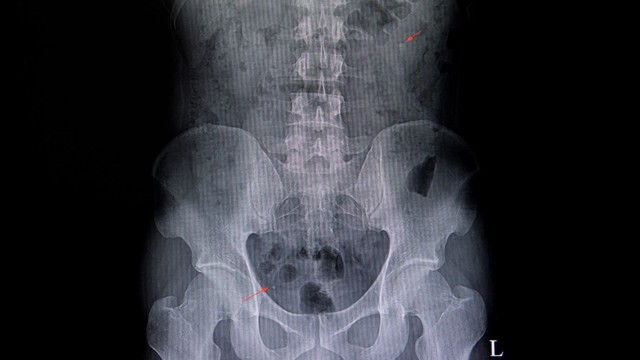

Sỏi tiết niệu